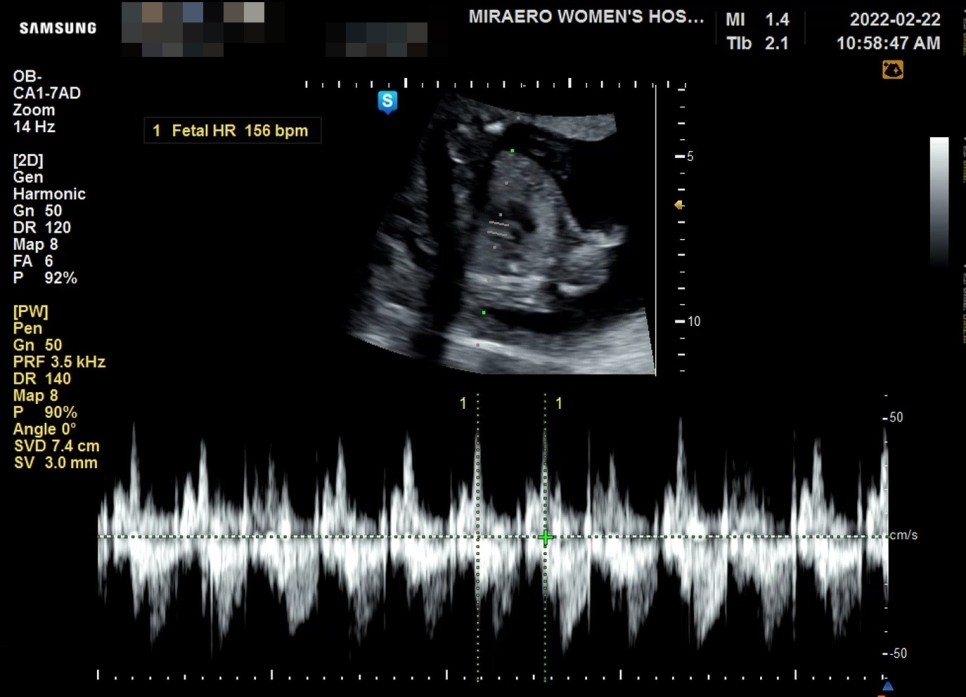

세상에서 제일 귀여운 연우(태아 이름)를 먼저 봤어요. 17주차 6일차 아기는 매우 잘 자라고 있었고 심장 박동도 156bpm으로 건강하게 달리고 있었습니다. 아랫배 통증은 자궁이 늘어나 자궁 쪽 인대에서 느껴지는 통증일 수 있다고 오히려 마지막 달보다 지금 먹고 싶어지는 느낌이 든다고 하셨습니다.

안쪽에 이상은 없는지 오랜만에 질 초음파로 한 번 안쪽을 보았습니다. 자궁경부의 길이와 양수의 양과 자궁 상태도 모두 문제가 없으면 아마 자궁 쪽 인대가 늘어나 그런 통증이 있었던 것 같다고 했습니다.